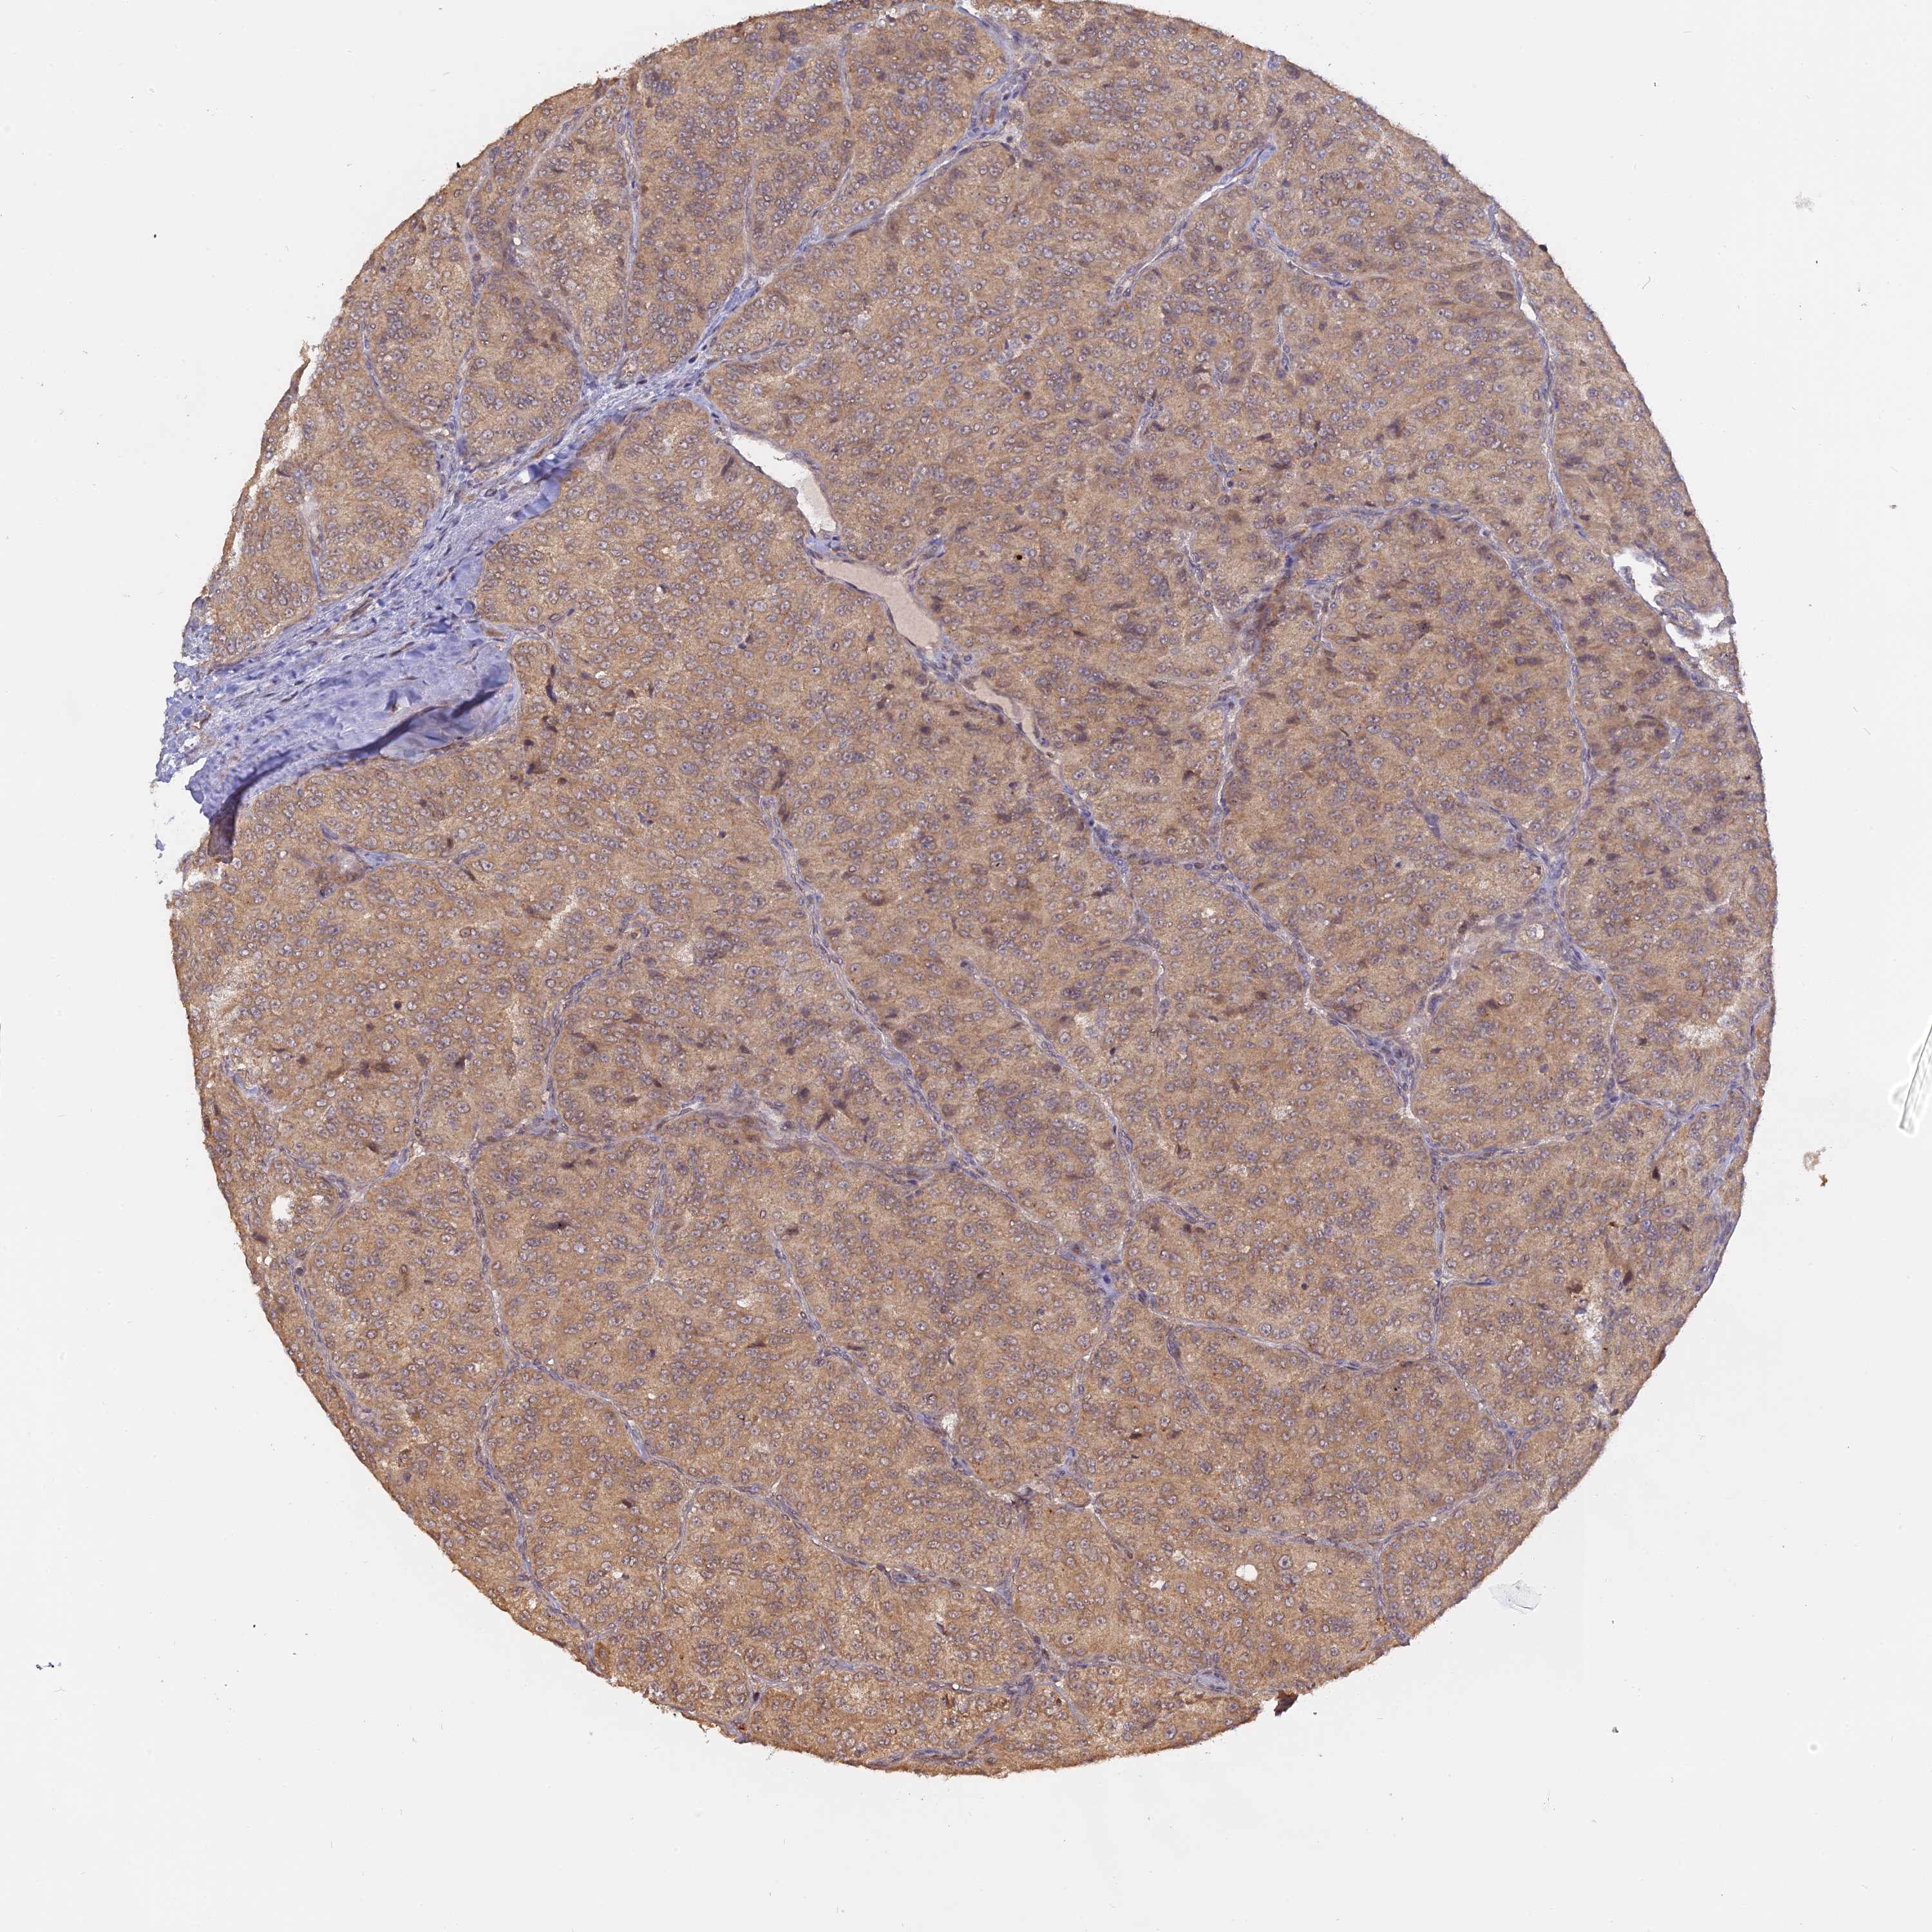

CANCER RENAL CANCER Show tissue menu

KICH TCGA KIRC TCGA KIRC VALIDATION KIRP TCGA PROTEIN RCC CPTAC PROTEIN EXPRESSION